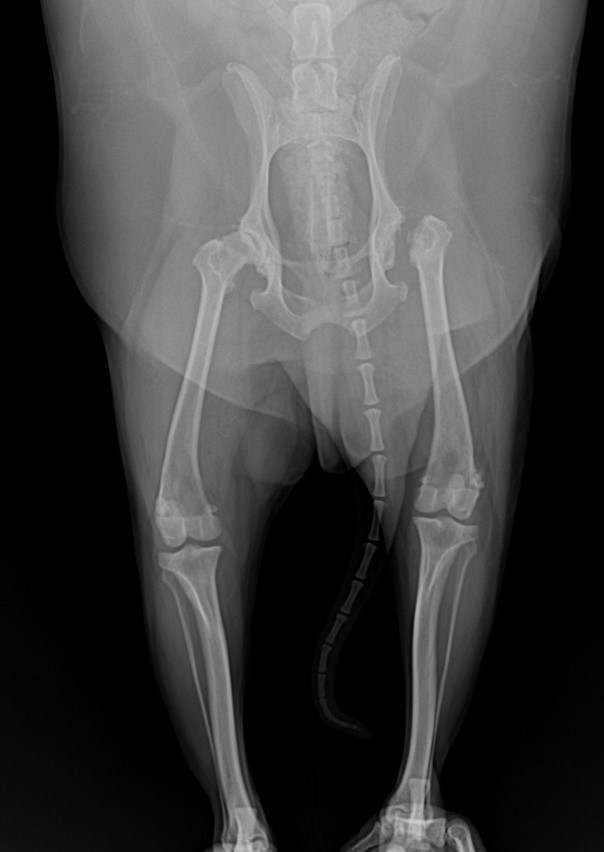

Phẫu thuật chỉnh hình

Phẫu thuật chỉnh hình được tiến hành để điều trị các vấn đề về cơ xương khớp ở thú cưng. Các vấn đề thường gặp phải trên thú cưng bao gồm: bị chấn thương do ngã hoặc tai nạn dẫn đến gãy xương, tổn thương dây chằng, viêm xương khớp, lệch xương bánh chè, thoát vị khớp…